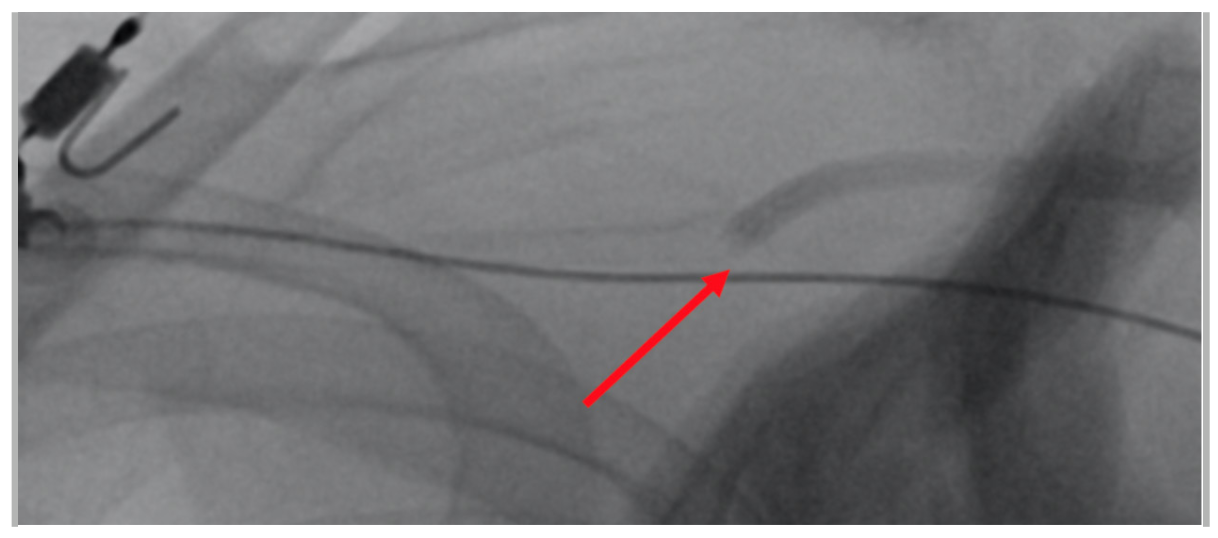

A 64-year-old female presented for closure of her left axillary access for intra-aortic balloon pump (IABP). We intended to close the access with standard balloon-assisted dry closure. A 7-Fr slender radial sheath was placed via left radial artery with a 7-mm peripheral balloon (Admiral; Medtronic) advanced to the subclavian artery. The IABP was removed over an 0.025-inch J-wire. There was already kinking noted at the entry site as indicated (Figure 1) due to adverse angulation. We failed to advance a Proglide device (Abbott) over an 0.035-inch wire due to kinking at transition zone of soft and hard part of the Proglide device (Figure 2).